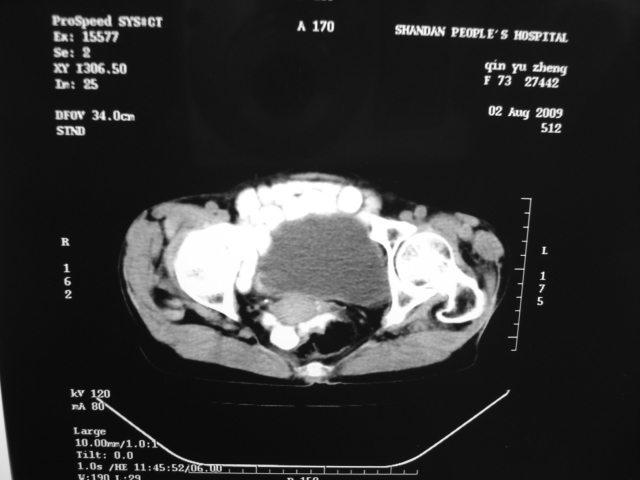

同事奶奶,73岁,腹痛一年,夜晚较重,潜血+++,拒绝增强,考虑左肾ca并腹膜后转移;请各位老师帮忙看看,谢谢!

左肾癌侵及输尿管上段,腹膜后多发淋巴结转移,脾脏钙化灶。至于潜血+++,要考虑消化道病变,本次ct片肠腔未见明显异常。

1)考虑左肾癌侵犯肾盂并腹膜后淋巴结转移。2)脾脏钙化灶。

考虑左肾癌侵犯肾盂并腹膜后淋巴结转移。